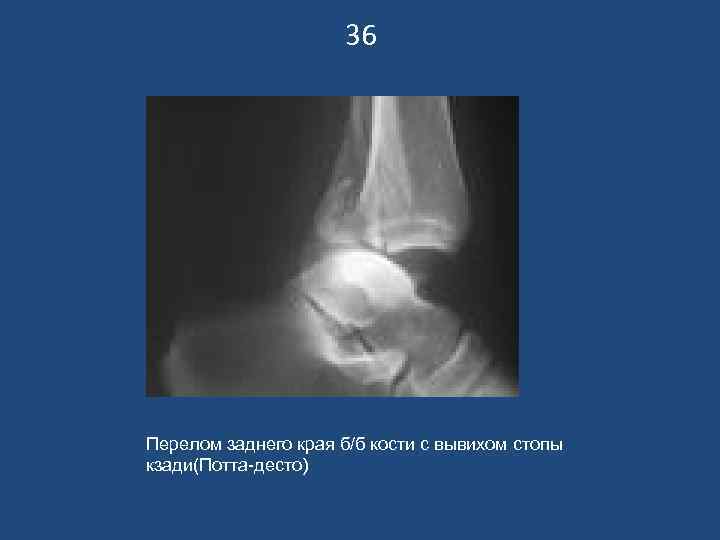

36 Перелом заднего края б/б кости с вывихом стопы кзади(Потта-десто)